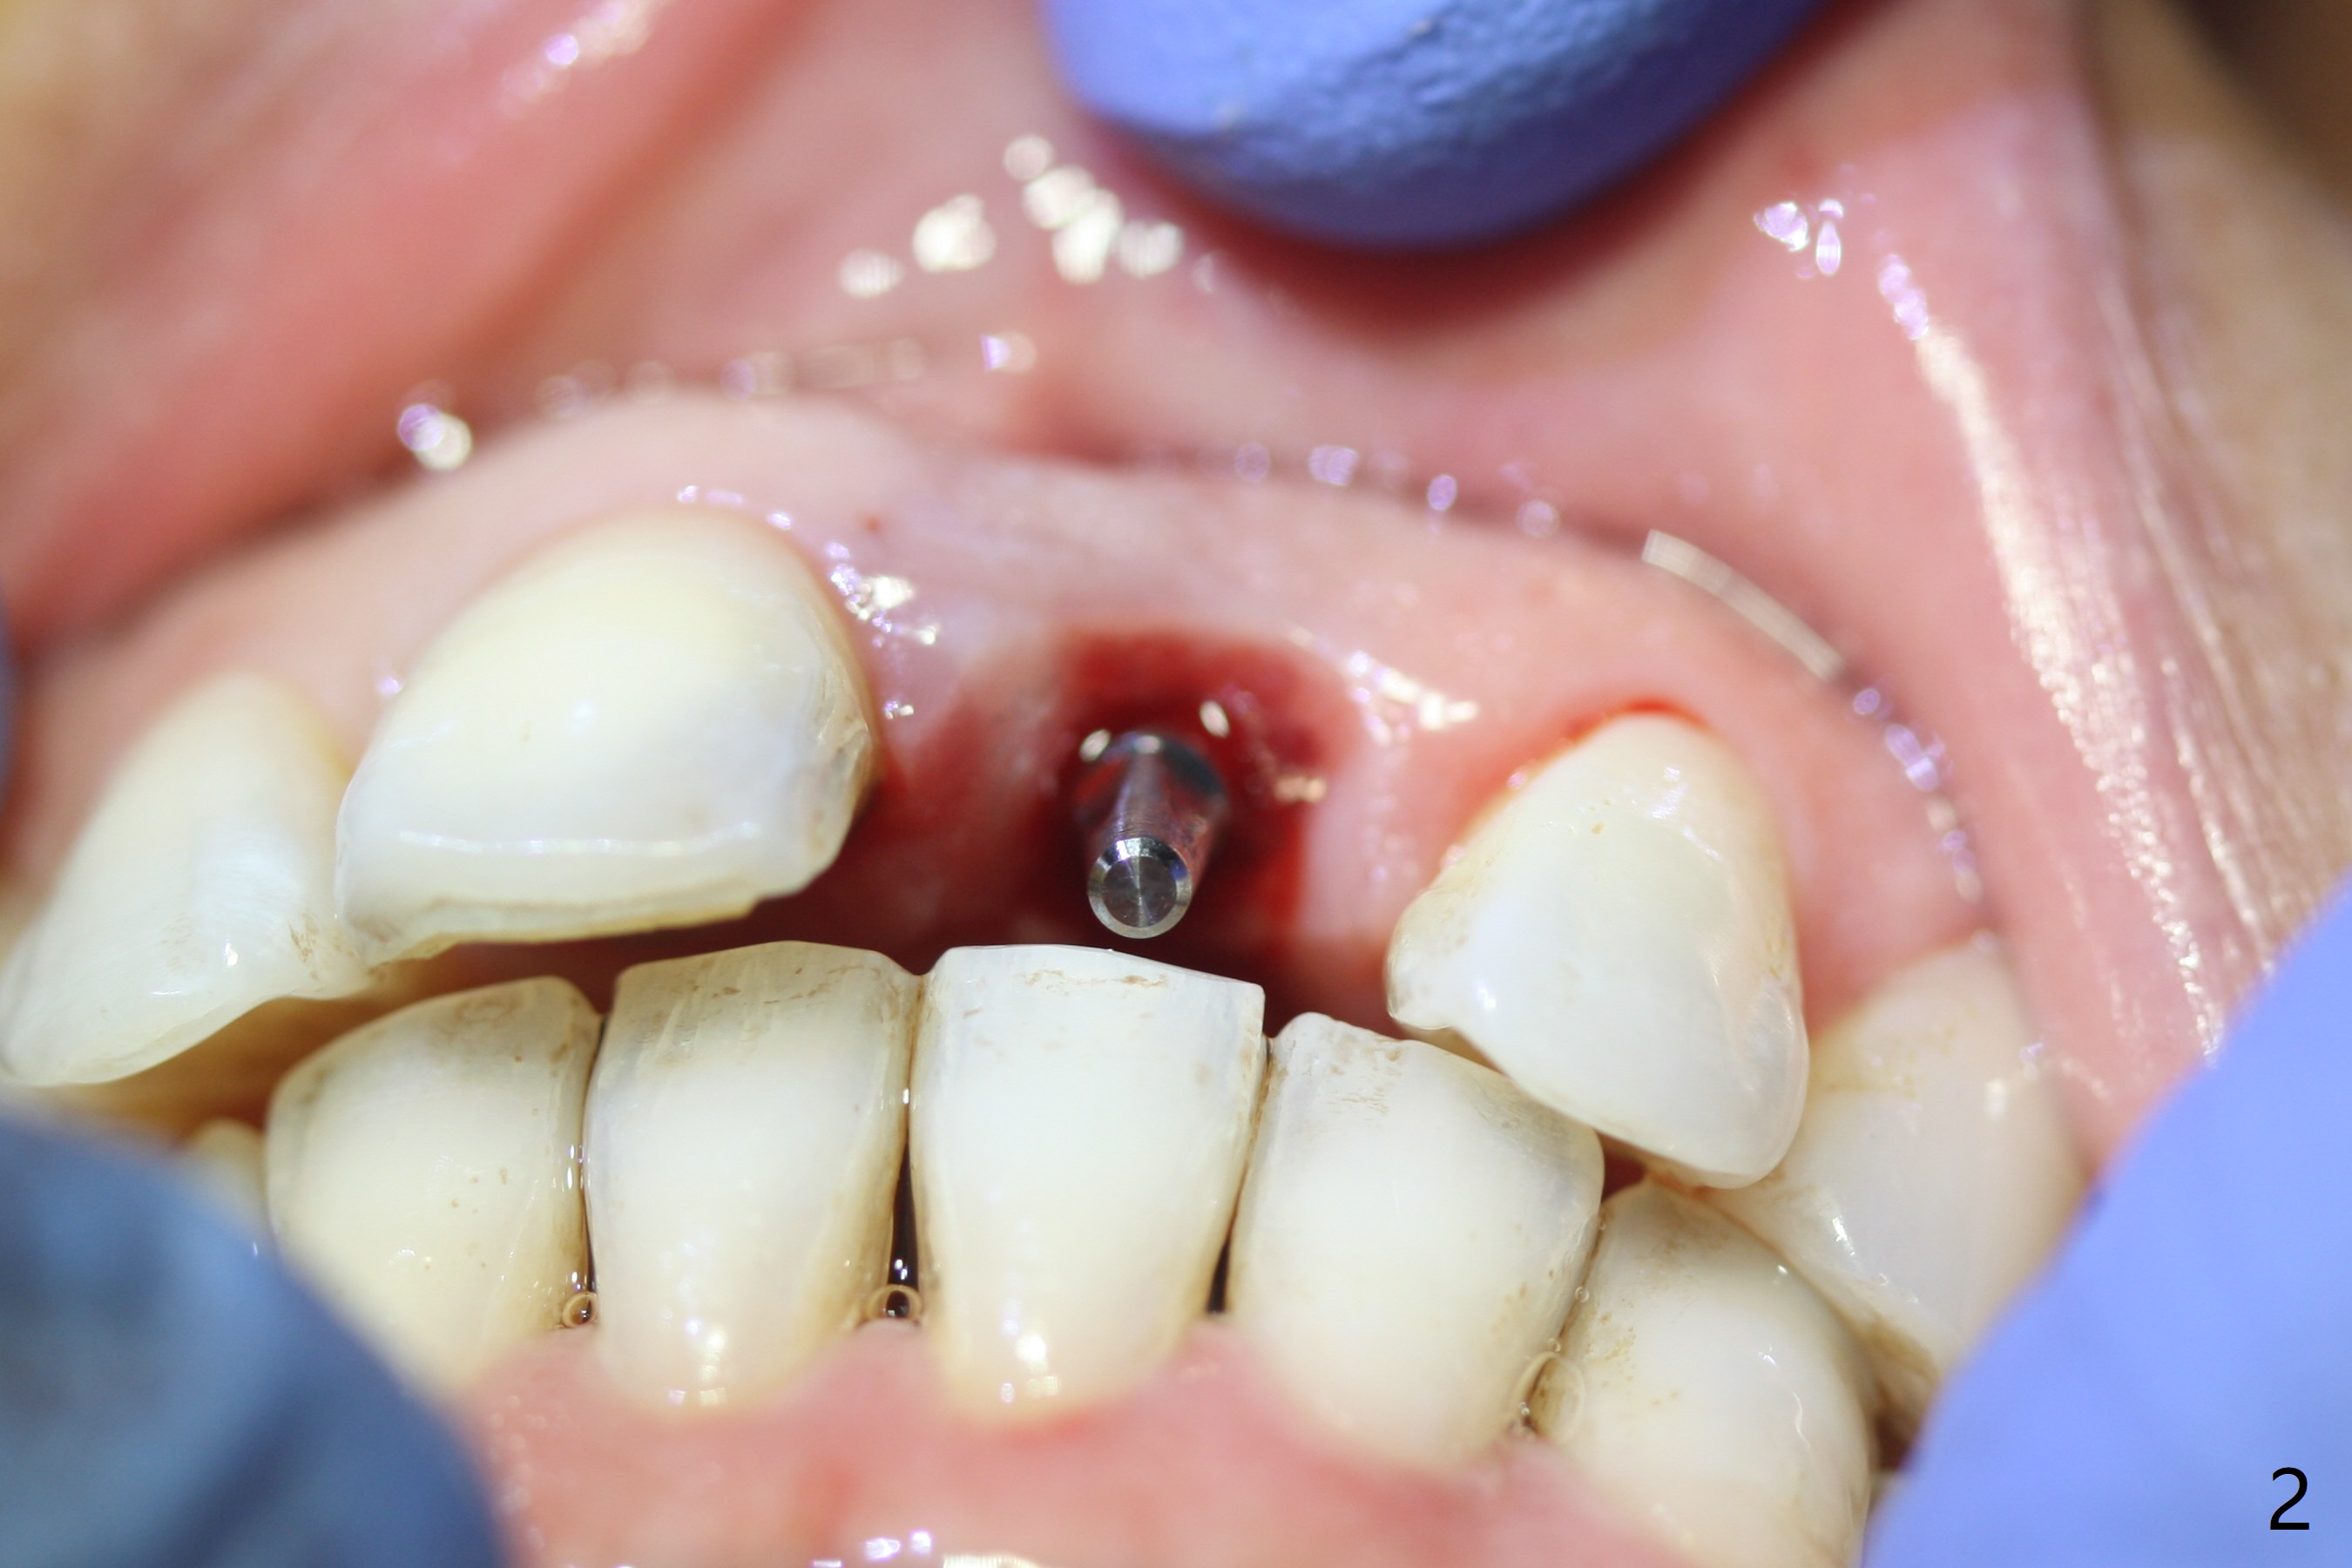

Except the depth, a 2.5x10 mm mini implant is placed with precision (in trajectory) at #9 (Fig.1-5). Confidence using surgical guide for the narrow ridge is enhanced due to placement of two digits against the buccal and palatal plates for tactile sensation. The depth issue is related to overprep with 2.2 mm drills. The torque is <15 Ncm. The immediate provisional is bonded to the neighboring teeth for retention. It appears that smaller drills should be made for guided surgery (such as 1.5 and 2.0 mm). The immediate provisional looks acceptable buccal and occlusal 3 weeks postop (Fig.6,7), although the palatal gingiva is erythematous (Fig.8, which is common after use of drill for access (tissue laceration), OHI offered). Three months postop (Fig.9), the palatal gingiva looks healthy (data not shown), while there is no bone loss around the implant (Fig.10). It remains the same 5 months postop (immediately post cementation, Fig.11) and 3,11 months post cementation (Fig.12,13). The labial gingiva is healthy (Fig.14), while the palatal one is less erythematous and edematous (Fig.15) than earlier (Fig.8).